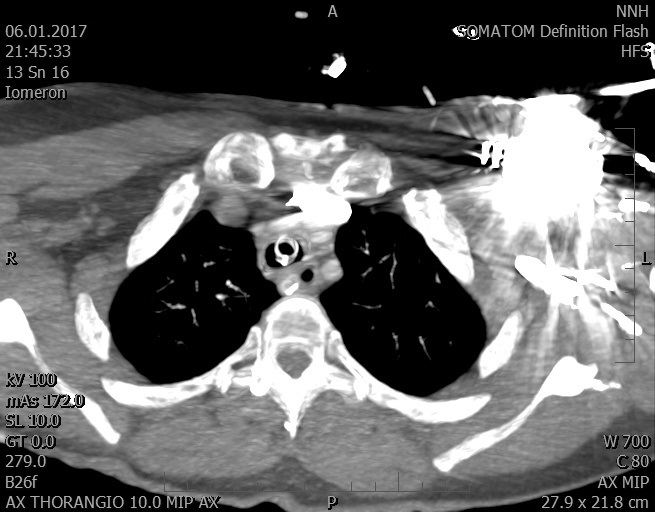

Video 2 - Echokardiograficky byla zjištěna těžká dysfunkce dilatační levé komory s nezvětšenou pravou komorou.Pro nejasnou příčinu zástavy jsme provedli i vyšetření výpočetní tomografií (CT), které vyloučilo plicní embolizaci (série 1 - soubory na konci článku). V den přijetí při přetrvávající oběhové nestabilitě byla nemocná opakovaně defibrilována pro fibrilaci komor se stabilizací rytmu po podání amiodaronu a mesocainu. Dle hemodynamických měření se jednalo o těžký kombinovaný šok. Vstupní laboratorní vyšetření bylo bez větších pozoruhodností. Posléze jsme doplnili anamnézu od příbuzných a zjistili, že pacientka užila do dvou hodin před srdeční zástavou první tabletu amoxicilinu na lehký respirační infekt. Při nevýtěžnosti vstupních vyšetření a nových anamnestických informacích jsme doplnili 14 hodin po kolapsu vyšetření koncentrace tryptázy v séru, která byla extrémně zvýšena (tabulka 2), což nás vedlo k podezření na anafylaxi.